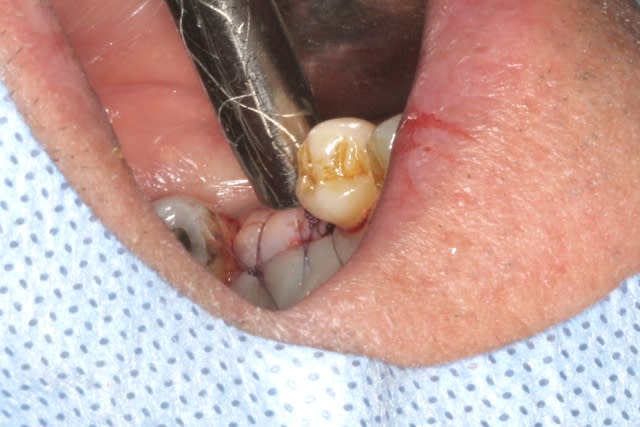

l'interactive, (t'ain qu'il est beau!!!)

mise en place au CA qui bloque à 45Ncm...on est à 1 ou 2 mm de la crête....pas de problème, on retire le Fm (sympa, la vis, car il y a un filetage dans le Fm, ne risque plus de tomber!!!) et on se reprend direct dans le col de l'implant à la clef à cliquet...comme d'hab quoi...;-)

mise en place de la vis de cicat basse pour augmenter l'épaisseur de gencive attachée et on suture par dessus...si çà s'operculise, c'est pas grave en plus